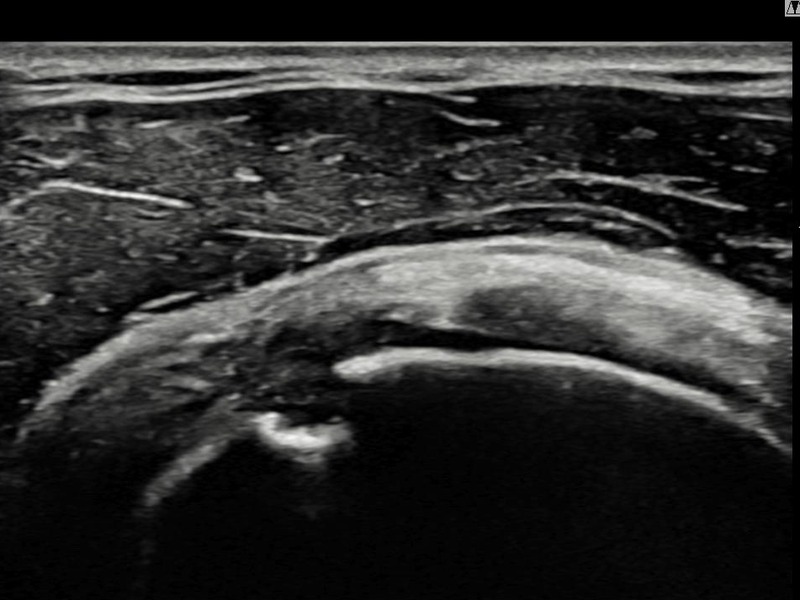

김ㅇㅇ님 · 우측 극상근건 관절면측 부분파열

우측 어깨 통증이 일상 동작에서 지속되어 내원하셨습니다. 초음파 검사에서 극상근건 관절면측 부분파열 확인 후 축소봉합술을 시행하였고 구조적 회복이 이루어졌습니다.

상세 보기 →